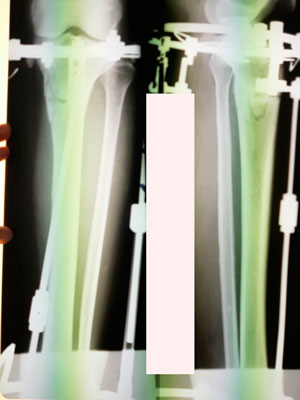

Рентген перед фиксацией.

Рентген перед снятием аппаратов